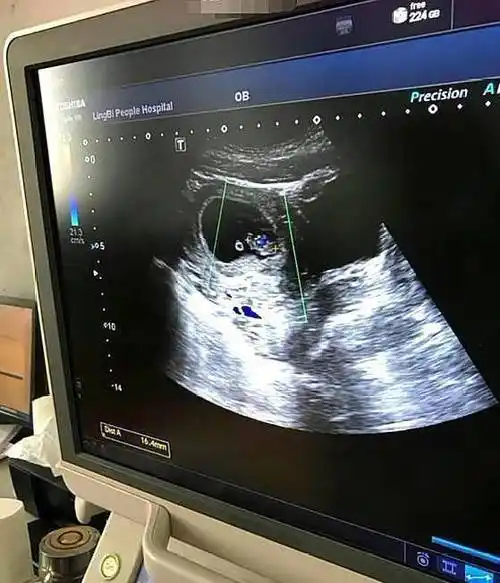

产科b超知多少

b超单上的一些信息,或许透漏了宝宝的"性别",孕妈别错过_胎儿_时候